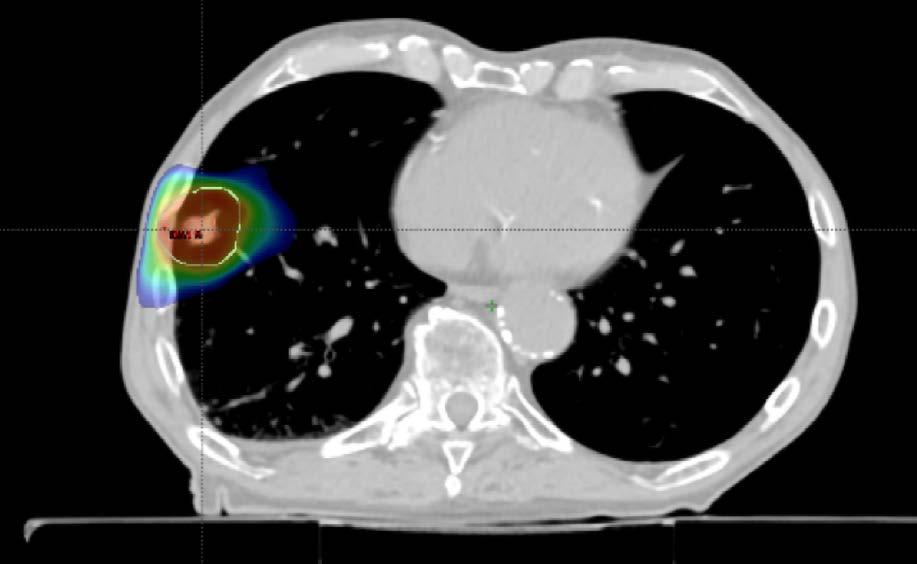

Mynd 6-1 Lítið lungnakrabbamein í hægra lunga (ör) sem fannst við skimun með tölvusneiðmyndum.

Með tilkomu tölvusneiðmyndatækni (TS) varð unnt að finna mun smærri hnúta í lungum en áður var mögulegt með hefðbundnum röntgenmyndum (mynd 6-1). Á síðustu áratugum hefur verið efnt til stórra framvirkra samstarfsverkefna, bæði í Bandaríkjunum og Evrópu. Fyrstu rannsóknir á skimun með TS voru gerðar í Japan og fyrsta alþjóðlega rannsóknin benti til þess að unnt væri að finna um